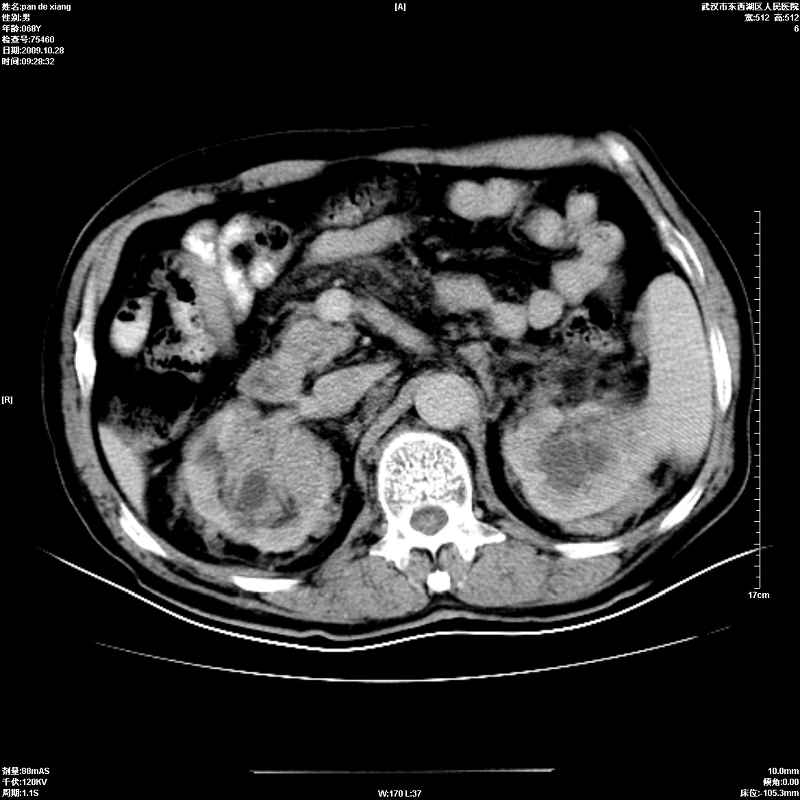

以下是引用杀毒软件在2009-10-28 20:41:00的发言:[br]结合临床考虑---白血病双肾改变或淋巴瘤。

以下是引用zxl51642在2009-10-29 9:59:00的发言:[br]结合临床“单克隆免疫球蛋白血症”,考虑双肾为继发损害并肾功能不全(尿中大量igg及少量iga、igm等大分子免疫球蛋白滤出所致继发损害),椎前软组织肿块为髓外造血。与浆细胞瘤有区别,平扫时有战友说的很清楚。